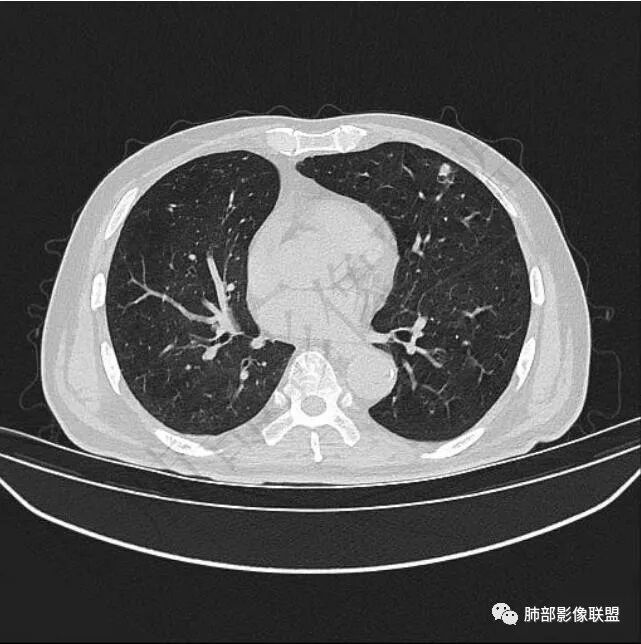

二..发现左肺上叶舌段实性密度小结节影,不规则略呈半环形,边界清楚,未见分叶、毛刺及磨玻璃晕。未见卫星病灶。

9个月后病灶明显增大,边缘较平直,部分膨隆,锁扣样外观,仍旧缺乏典型深分叶及张力,未见胸膜凹陷。

再1个多月后病灶继续增大,较明显不均匀强化,肺门一侧见低密度区。病灶边缘相对不清,可见毛刺。